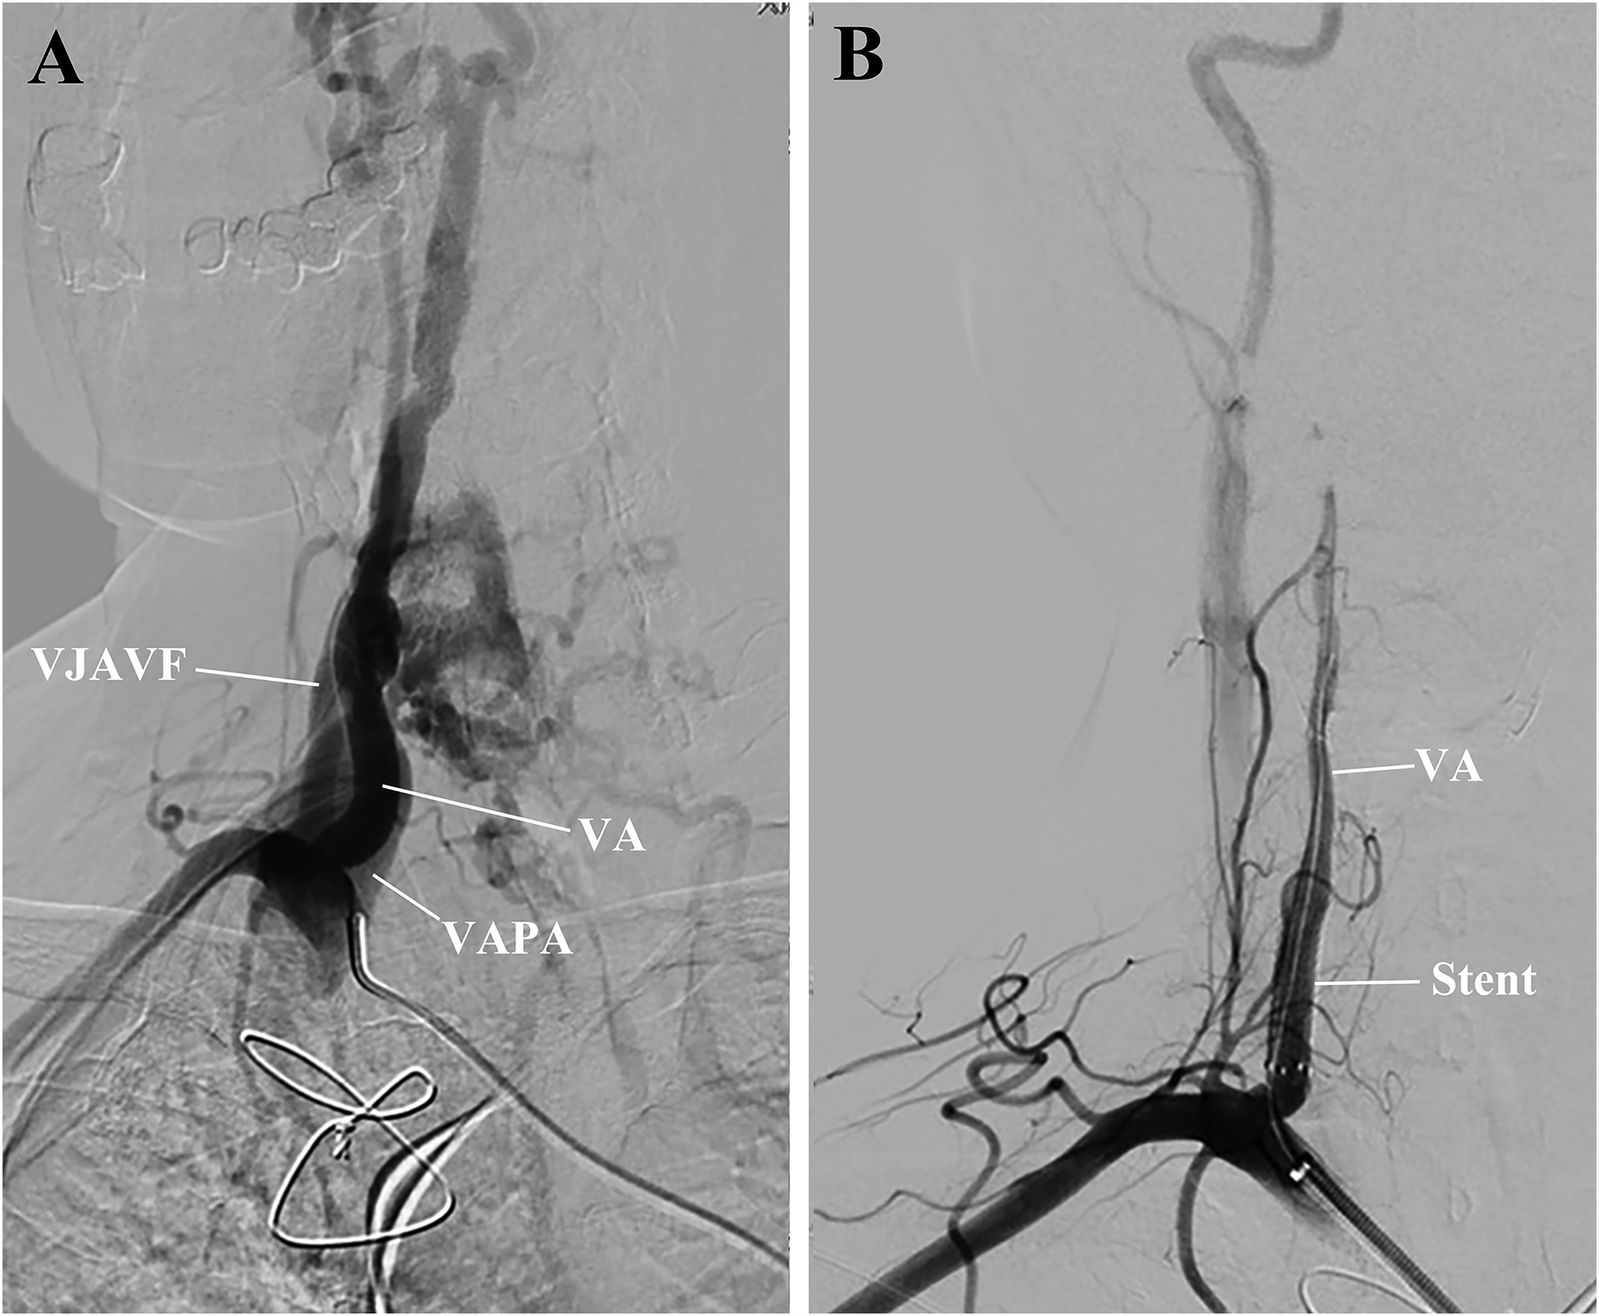

After informed consent was obtained from the patient, a 6 Fr Neuron Max catheter was introduced into the right subclavian artery via the left femoral approach, and a selective right subclavian arteriography was performed (Figure 2A). With the aid of a 6 Fr guiding catheter and soft guidewire, the Neuron Max catheter was advanced to the V1 segment of the right VA, while the soft wire was advanced into the distal V2 segment. A VIABAHN delivery catheter loaded with an endovascular prosthesis (W.L. Gore & Associates, Inc., USA) was advanced into the distal V2 segment over the wire. A 4 mm stent graft coated with a heparin bioactive surface was deployed in a 3.6 mm VA to cover both the VJAVF and the VAPA ostia (Figure 2B).

Figure 2

Preoperative and postoperative right subclavian arteriography. (A) The exact origin of the VJAVF and VAPA and the diameter of the VA were carefully determined. Collateral circulation was noted in this area. (B) After the procedure, the angiograms revealed a complete sealing of the VJAVF and VAPA, improved distal flow of the VA, and reduced collateral circulation. VA, vertebral artery; VAPA, vertebral artery pseudoaneurysm; VJAVF, vertebrojugular arteriovenous fistula.